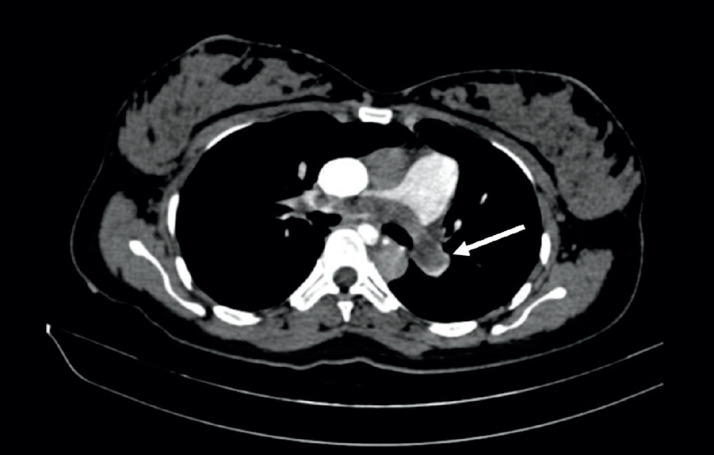

Case presentation: Case 1: A 39-year-old pregnant woman at 36 weeks and 5 days of gestation with central placenta previa was admitted due to antepartum hemorrhage. She developed convulsions and cardiac arrest during a cesarean section, requiring cardiopulmonary resuscitation. Laboratory tests revealed severe anemia, thrombocytopenia, coagulopathy, severe acidosis, and myocardial injury. Bedside echocardiography and CT scan identified high-risk pulmonary embolisms. Intensive care included VA-ECMO, CRRT, transcatheter arterial embolization, and mechanical thrombectomy. Histopathology confirmed amniotic fluid components making up the emboli. Case 2: A 31-year-old female was transferred following a cesarean section for central placenta previa complicated by severe hemorrhage, cardiac arrest, and pulmonary embolism. Laboratory results showed severe anemia, thrombocytopenia, significant coagulopathy, myocardial injury, and hepatic injury. Histopathology confirmed amniotic components in the embolism. Management involved extensive blood transfusions, and pulmonary thromboendarterectomy. She was discharged in improved condition.